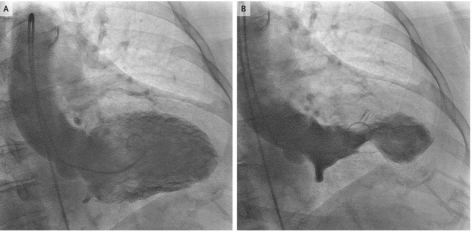

Today, we discussed the case of an elderly woman with significant history of vasculopathy and ESRD who presented with weakness, found to be bradycardic to 30s, hypotensive, and hyperkalemic to 7.2. Her hyperkalemia was treated with dialysis but she underwent cardiac cath due to up trending troponins, found to have a 100% occlusion of the RCA!

In our patient, the cause was severe hyperkalemia as well as an RCA infarct. Given her clinical instability, and the potential for worsening hyperkalemia from cardiac catheterization alone, the team normalized her serum potassium before performing cardiac cath which led to the RCA MI diagnosis.